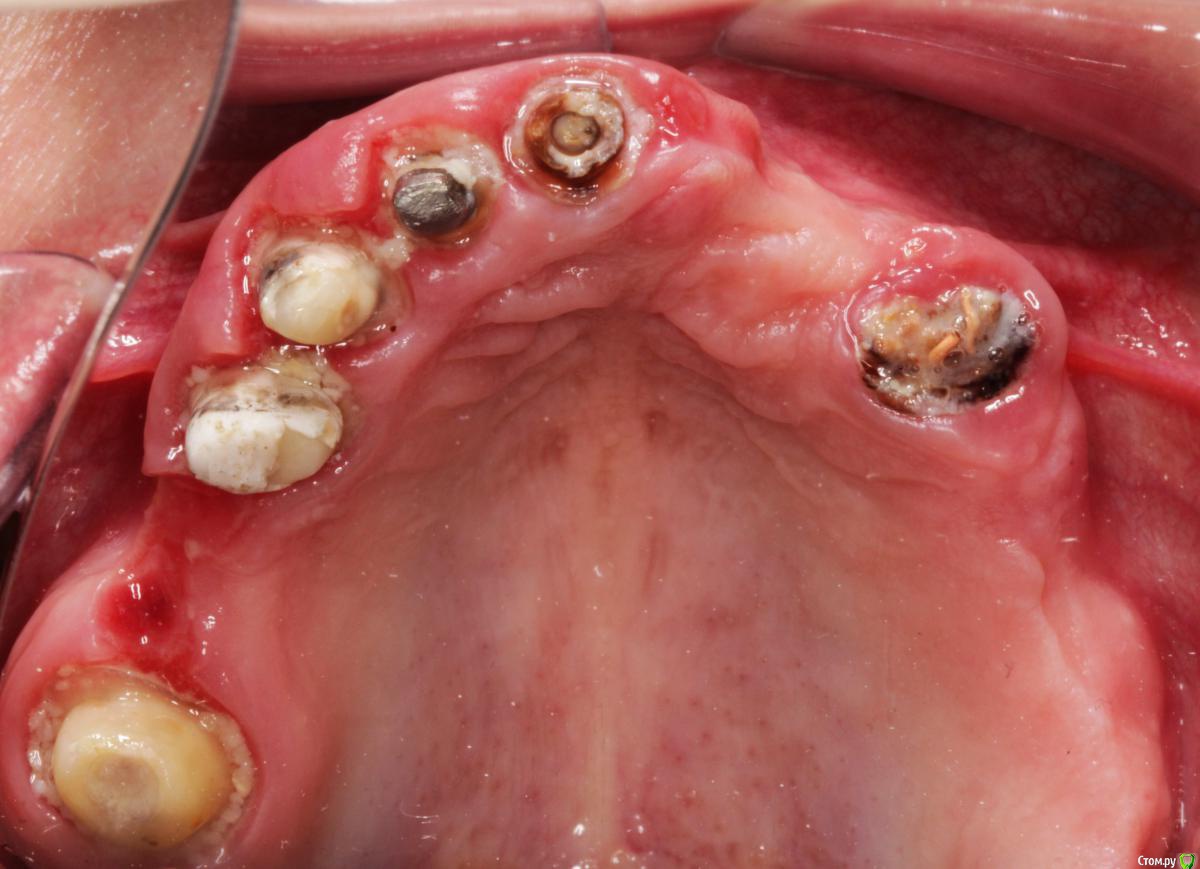

Витторио Орлионе Опубликовано 24 июня, 2019 Поделиться Опубликовано 24 июня, 2019 (изменено) Здравствуйте, уважаемые коллеги, позвольте обратиться за советом.Ситуация такова: 3 месяца назад были удалены все корни зубов на верхней челюсти, установлены 3 импланта MIS seven 1.4, 1.1, 2.6 с заглушками торк на момент установки составлял 35-40 Н/см, а взамен всех остальных нкр Biooss S, Biogide в связи с дегистенциями в области удаленных корней 1.6, 1.3, 2.4. Через 3 месяца планируется имплантация ещё 3 импланта с немедленной нагрузкой. А пока можно ли уже сейчас сделать временную конструкцию без вреда для костной пластики и какую? Изменено 24 июня, 2019 пользователем Витторио Орлионе Ссылка на комментарий

Витторио Орлионе Опубликовано 27 июня, 2019 Автор Поделиться Опубликовано 27 июня, 2019 А все сразу вместе с несъемными времяшками на имплантах побоялись делать?Насколько нужна временная конструкция пациенту если уже согласился 3 месяца ходитьтам была целая история, получилось так, что ещё три имланта в области 1.6, 1.3 и 2.4 сильно заглубил, после удаления были дегистенции вестибулярно, а мембан не было для их закрытия, в итоге эти импланты выкрутил и НКР, а пациентКА - родственница, жалуется на то что язык некуда деть, нижняя челюсть устаёт, жевать хочется, смеяться и улыбаться. Ссылка на комментарий